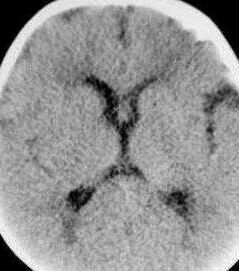

3.肺炎雙球菌腦膜炎發病事較高,僅次於流腦,多見於1歲以下嬰兒,常於冬春季節繼發於呼吸道炎症、敗血症或顱腦外傷等,早期頸項強直不明顯,病程可遷延或反覆發作。可並發硬膜下積液或積膿、腦膿腫、腦積水等,一般病情較重。

(2)腦脊液壓力增高,外觀混濁或為膿樣。細胞數明顯增多,中性粒細胞占絕大多數,糖定量減低,蛋白顯著增加。腦脊液塗片可檢得病原菌。